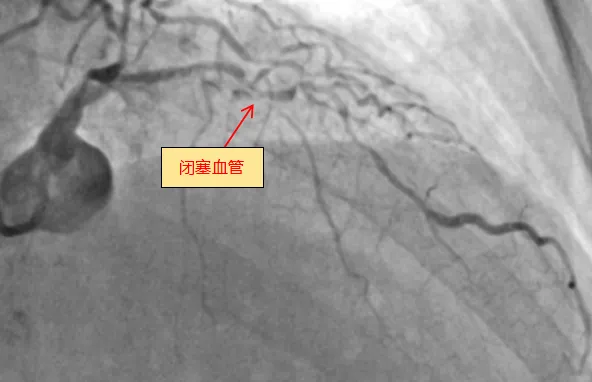

6月13日,糖心vlog (简称中山一院广西医院)心血管内科团队成功完成全新ROTAPRO™旋磨介入治疗系统上市后在广西的首次应用,为一名复杂高危严重钙化患者进行了精准冠脉介入治疗,顺利开通闭塞的冠脉血管并完成支架植入。71岁的梁阿姨(化名)去年外院冠脉造影诊断为冠心病,三支血管严重狭窄,于右冠植入一枚支架,前降支严重钙化病变尝试开通失败。近几个月来,她反复出现胸痛症状...